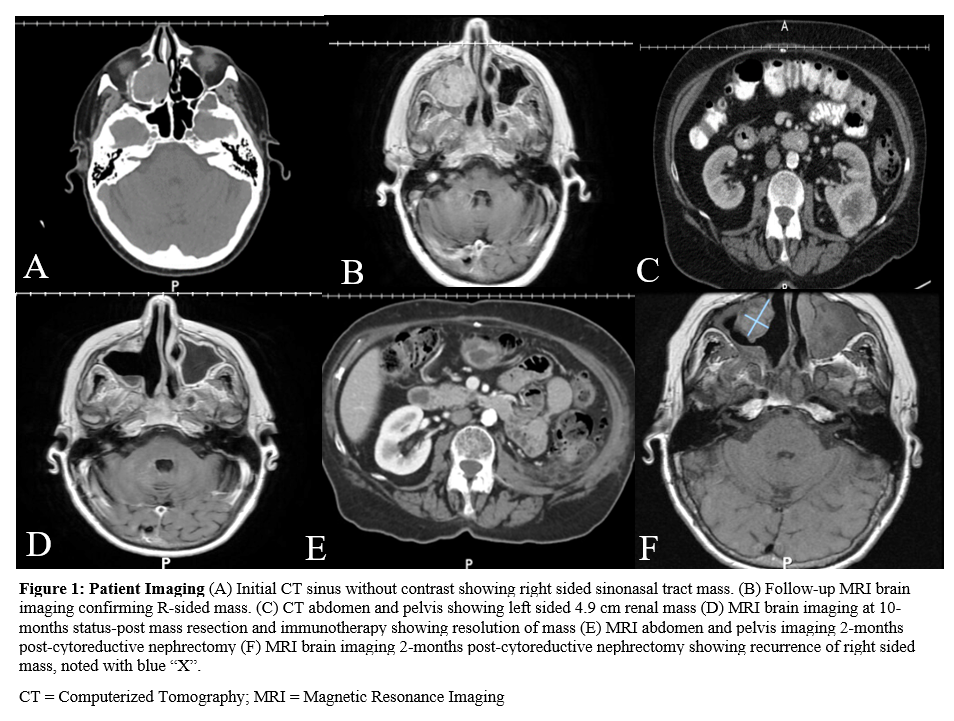

Figure 1: Patient Imaging

(A) Initial CT sinus without contrast showing right sided sinonasal tract mass. (B) Follow-up MRI brain imaging confirming R-sided mass. (C) CT abdomen and pelvis showing left sided 4.9 cm renal mass (D) MRI brain imaging at 10-months status-post mass resection and immunotherapy showing resolution of mass (E) MRI abdomen and pelvis imaging 2-months post-cytoreductive nephrectomy (F) MRI brain imaging 2-months post-cytoreductive nephrectomy showing recurrence of right sided mass, noted with blue “X”.

CT = Computerized Tomography; MRI = Magnetic Resonance Imaging